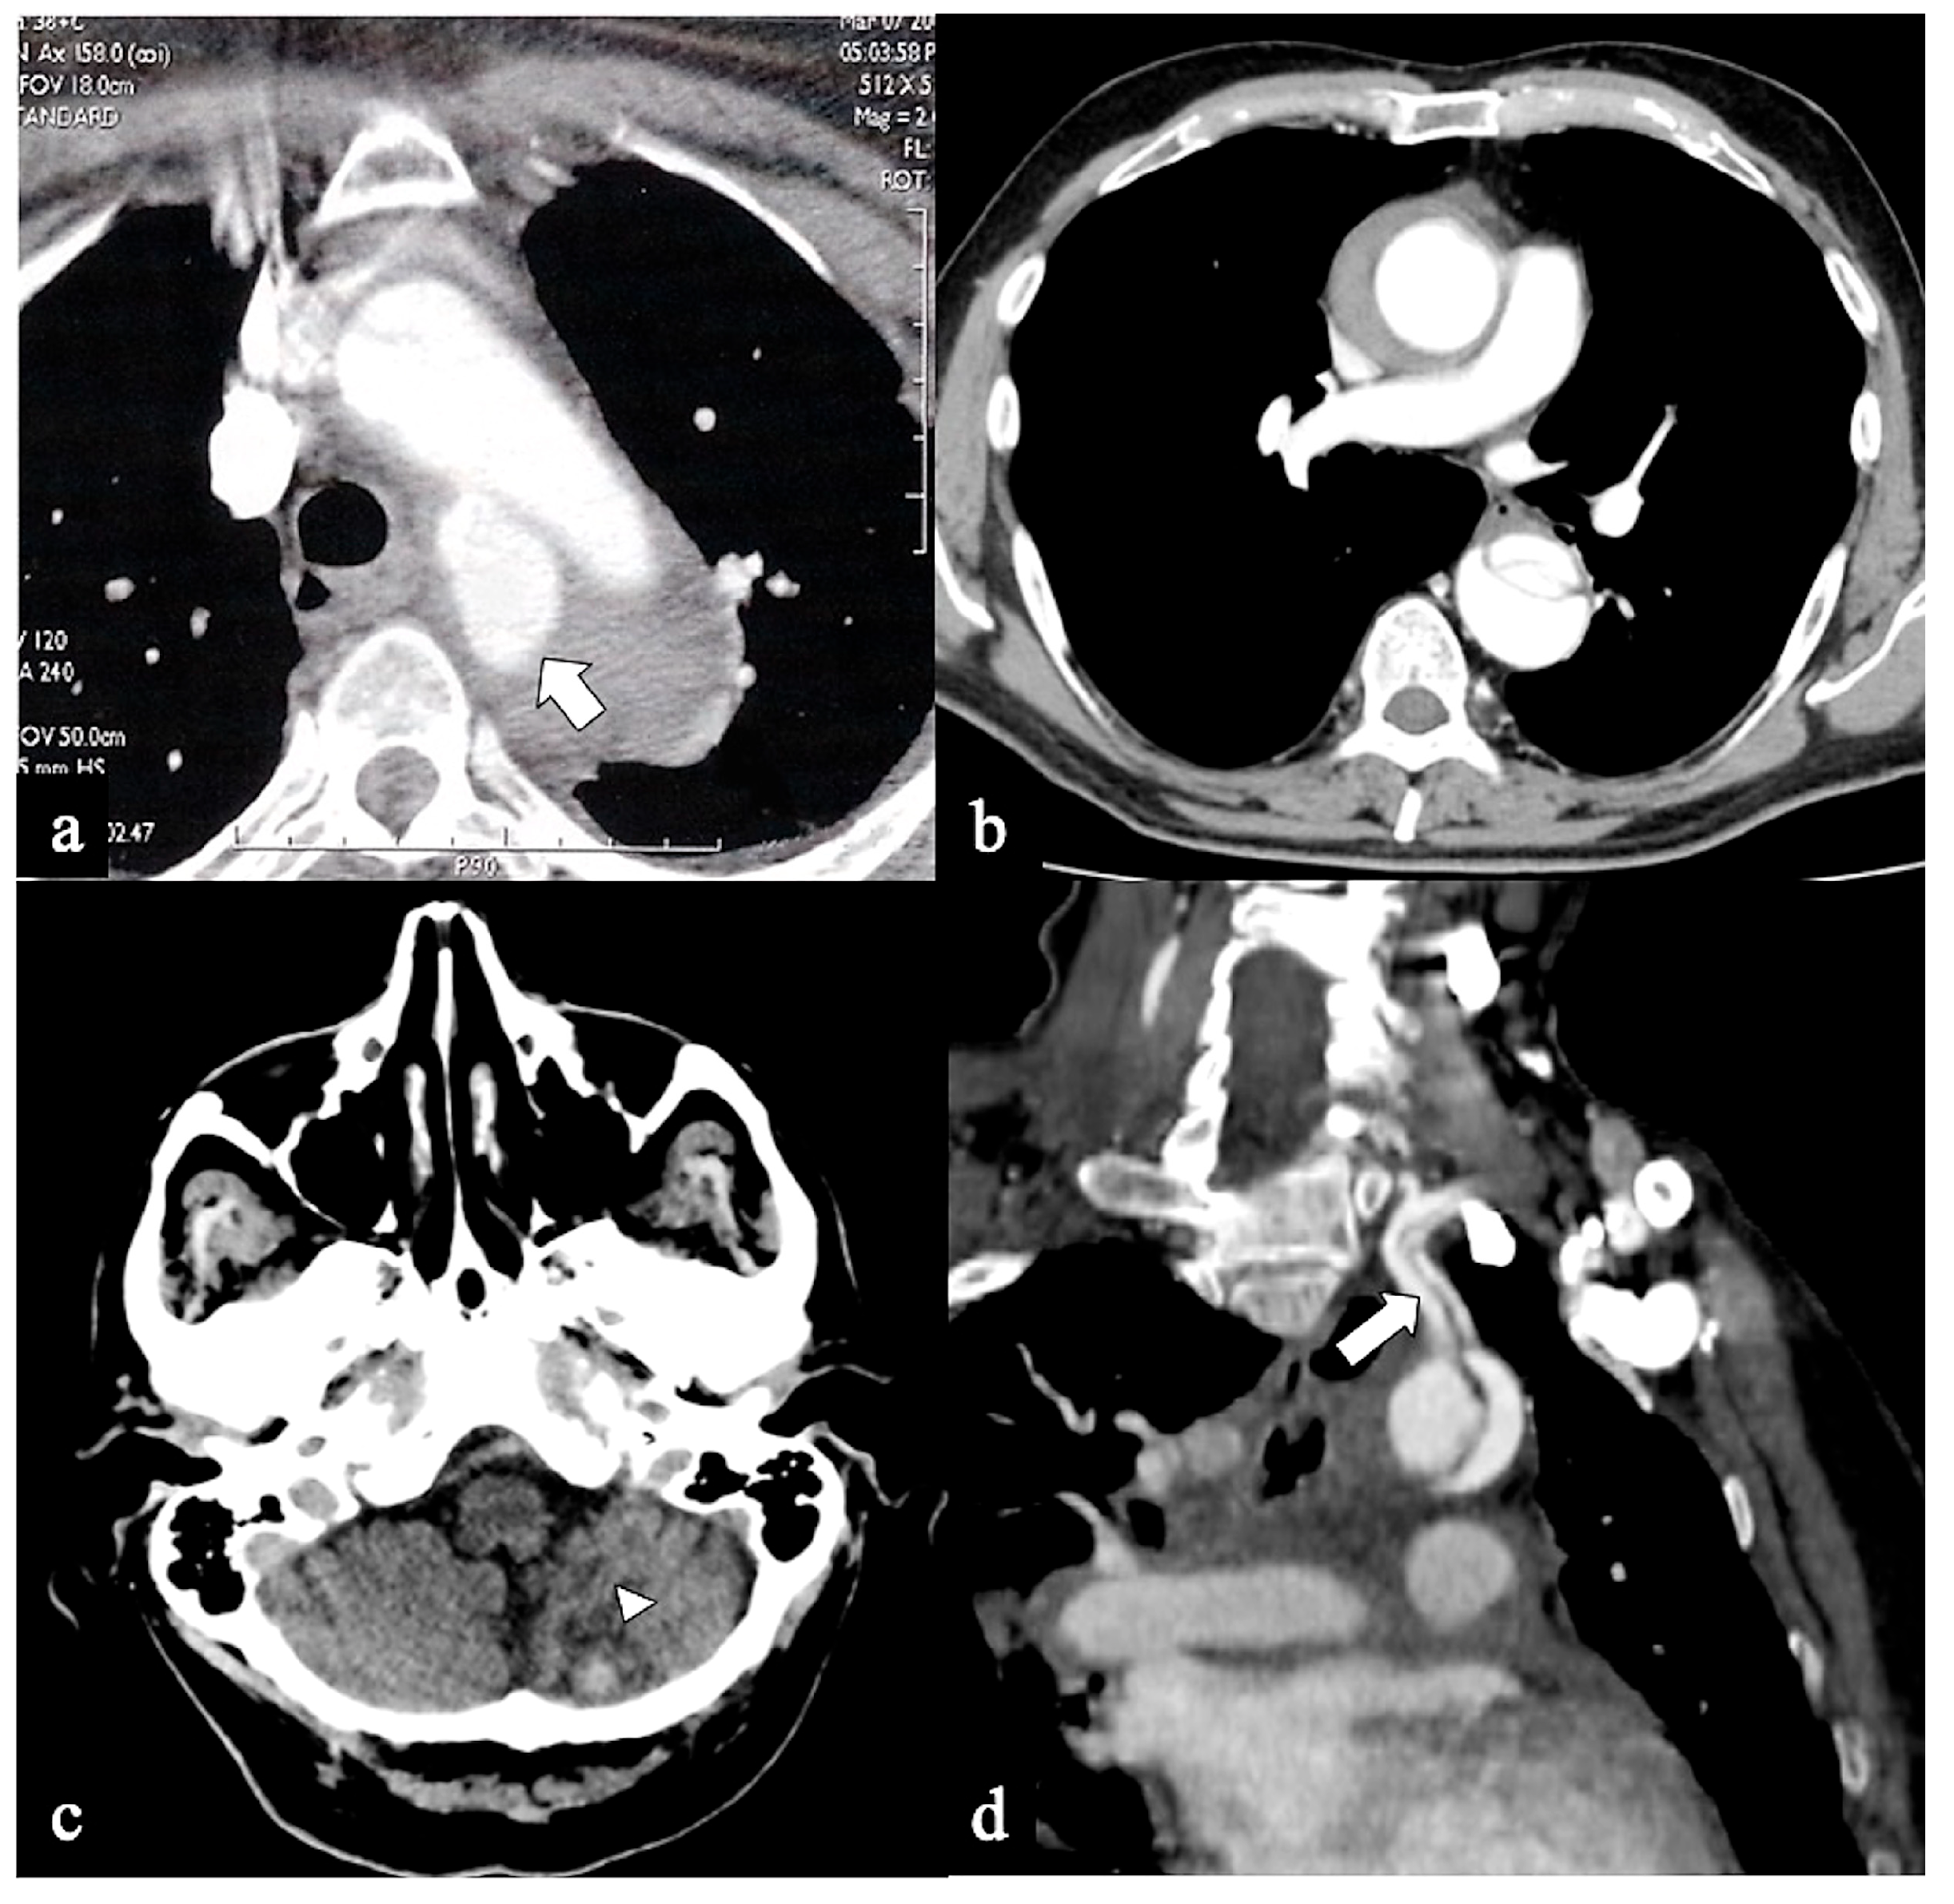

- Configuration 1 (or DTA entry): Among the cohort, 25 out of 36 patients (69.5%) presented with a type B AD or descending-entry type, with the primary entry tear distal to the left subclavian artery (zone 3). The extension of the flap occurred antegradely into the descending aorta, with or without the involvement of the abdominal aorta, and retrogradely into the aorta until the brachiocephalic trunk (BCT) (Figure 3). We describe this configuration as non-A non-B dissection with a retrograde pathway of dissection, as the entry site of the flap is in the descending aorta with retrograde arch involvement. According to Stanford classification, this configuration was present in 14% of type B AD patients. Previous studies have documented DTA entry type to be present between 10% and 25% of patients with acute type B dissection, sometimes as an intramural hematoma [33,34,35]. Patients presenting with DTA entry non-A non-B dissection demonstrated a prevalent origin of BCT and LCCA in 20% and an arch origin of the left vertebral artery in 4%. Among these cases, the distal extent of dissections was observed in various locations: the thoracic aorta in 9 patients, the abdominal aorta in 7 patients, and the pelvic circulation in 9 patients. Involvement of specific arteries was noted, including the left subclavian (n = 5), left common carotid (n = 1), or innominate (n = 1) arteries. Six of these DTA entry patients, who were initially managed with medical therapy, necessitated hybrid or surgical aortic repair within 10 days after the onset of dissection due to persistent pain (3/5), new organ malperfusion (2/5), or rapid aortic growth (1/5). Forty percent of these patients underwent treatment with optimal medical therapy and close imaging surveillance, while 60% received hybrid or open surgical therapy.